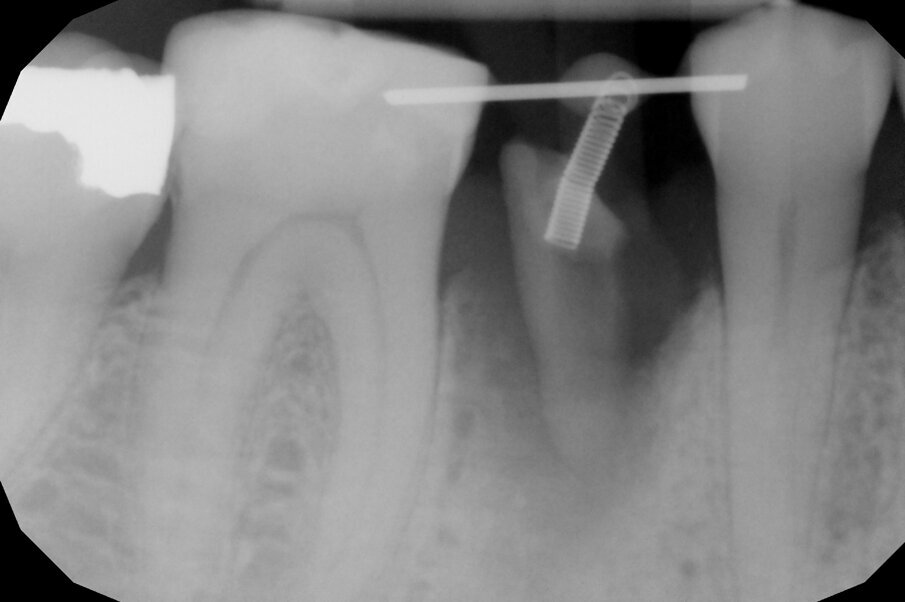

Per ottenere questo risultato nel gennaio 2021 è stato ancorato un segmento di arco in acciaio a sezione quadrata 0.021” x 0.025” agli elementi 4.4 e 4.6 per mezzo di composito. Il segmento è servito da ancoraggio per una molla con forza di trazione 150 g in posizione obliqua in senso disto-mesiale.